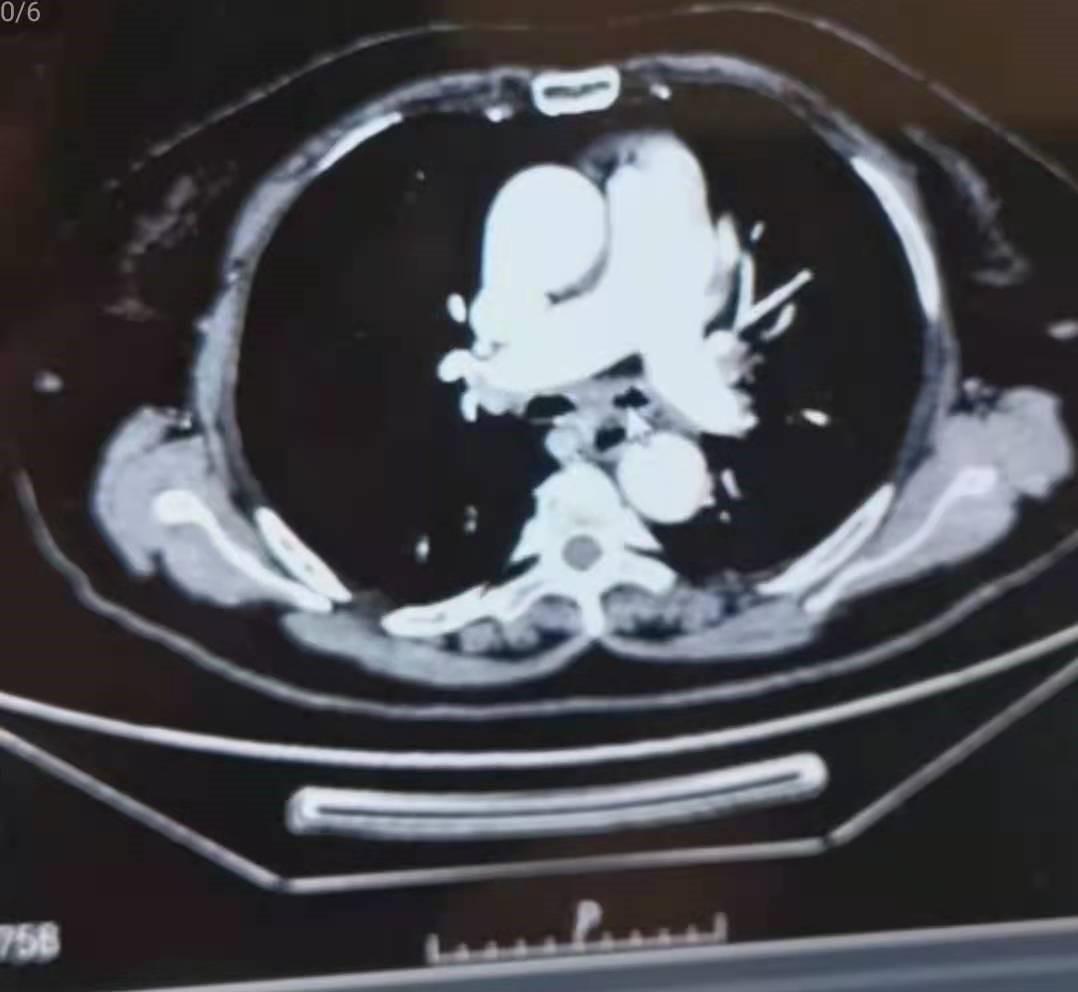

支气管动脉灌注治疗之后

经过手术后,患者情况得到好转,通过片子我们可以看到分叉的地方肿瘤都变得非常小,虽然没有治愈患者,但是我们用这些手段让病人的痛苦大大的减小生存期也得到了延长,这就是我们治疗的目的,看到患者情况好转,有了很大的恢复,患者儿子告诉我们,这已经超出了他们的预期,虽然没有彻底治愈他的父亲,但是让他们看到希望,给了他们在绝望中一缕曙光,也能够给他们一些陪伴父亲的时间。